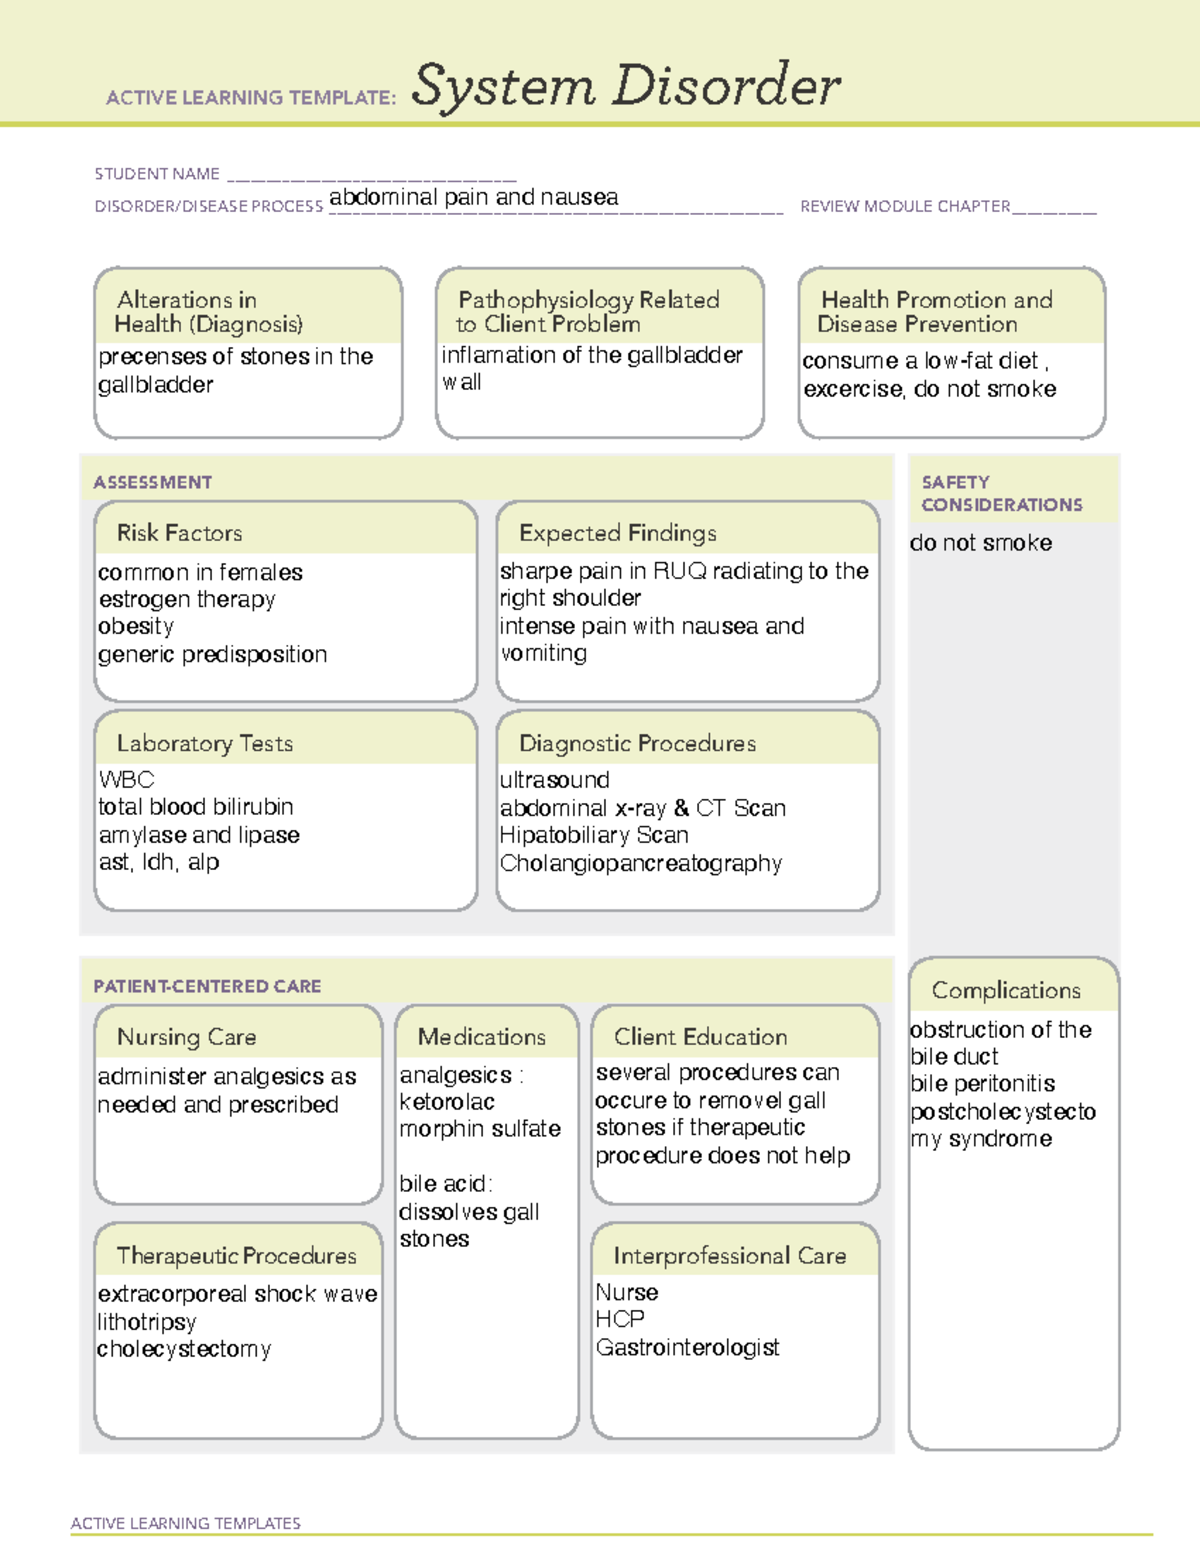

Abdominal Pain Nausea ATI ACTIVE LEARNING TEMPLATES System Disorder